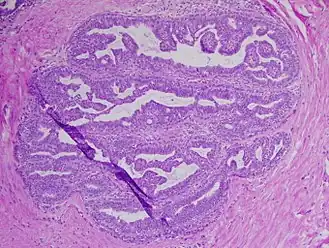

Image histologique de papillome urothélial.

Papillome urothélial inversé de la vessie. HE, x400.

- Papillome urothélial : lésion urothéliale composée d'axes conjonctifs bordés par des cellules urothéliales, rappelant la structure des « papilles ». Il peut être exophytique ou inversé, dans ce dernier cas les cellules épithéliales proliférantes s'invaginent dans le stroma sous-jacent[1].